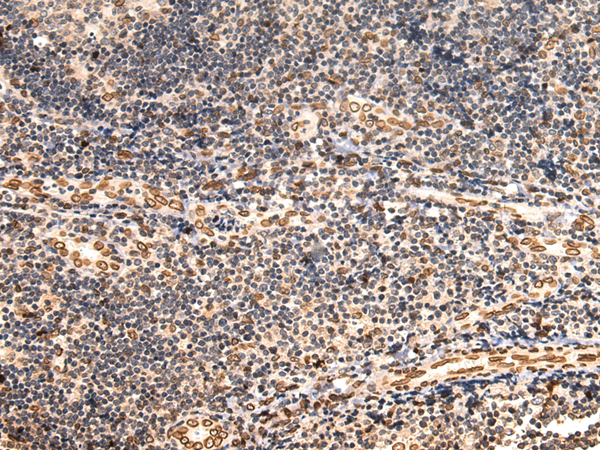

分类: 科研抗体货号: P07421别名: LMN; ADLD; LMN2; LMNB应用: WB,IHC反应种属: Human, Mouse, Rat

分类: 科研抗体货号: P07429别名: MAD1; PIG9; TP53I9; TXBP181应用: WB,IHC反应种属: Human, Mouse

分类: 科研抗体货号: P07420别名: GRH; GNRH; HH12; LHRH; LNRH应用: IHC反应种属: Human